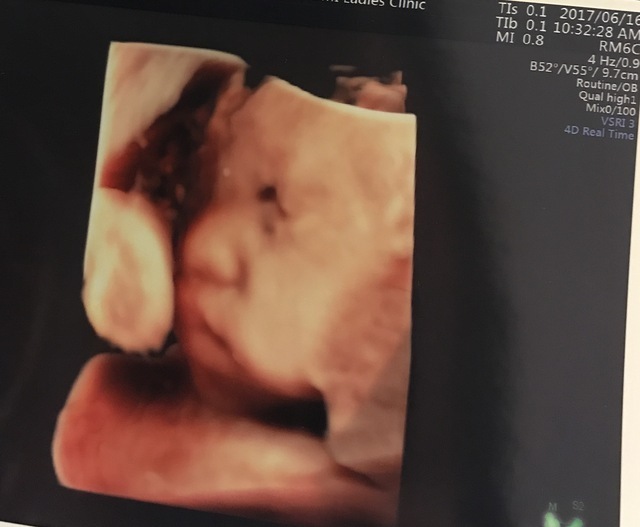

32週4日(32w4d・女の子)|あいたかそう さん(28歳)

エコー写真撮影時のエピソード:

2回目の3Dで横顔がとってもかわいく撮れました。ずっと性別が分からず、後期になって女の子と言われました。でも最初の子が男の子だったこともあり、生まれてきたら男の子かもよと話していた時期にこのエコー写真を見て、顔つきが女の子だったので確信が持てたのを覚えてます。